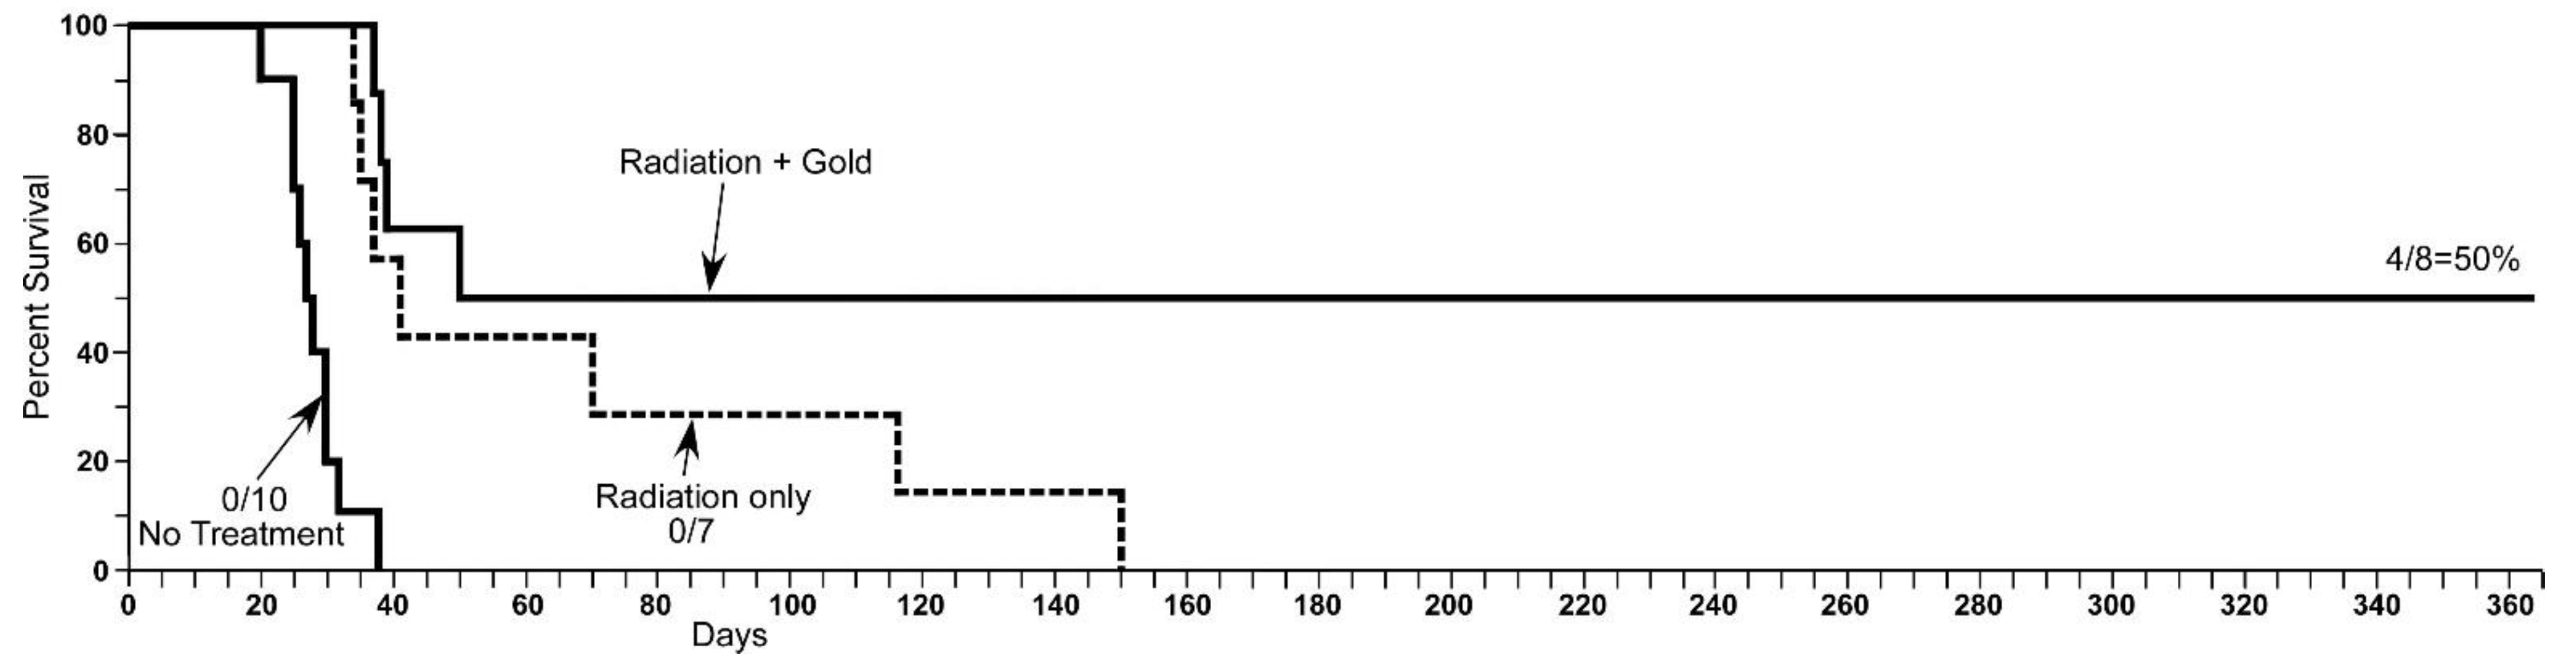

1.5. Iodine Nanoparticle Glioma Therapy